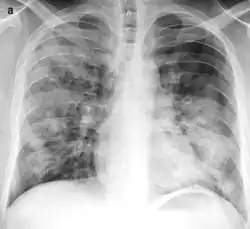

Radiografía torácica mostrando una prominente área de consolidación aérea cuneiforme en pulmón derecho, característica de la neumonía lobar aguda.

Placa torácica mostrando consolidación pulmonar multifocal y bilateral, característica de la bronconeumonía. -